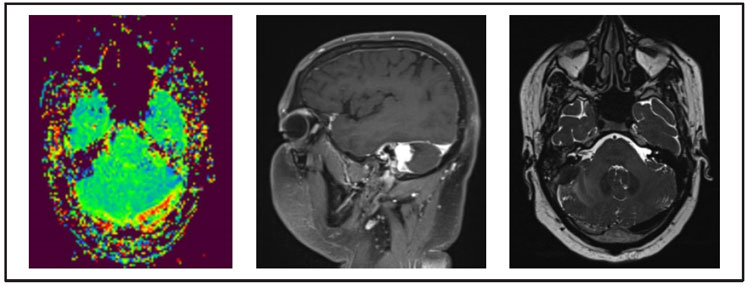

Figure 1: Magnetic resonance images, MRI on the bottom right and left images, and MR spectroscopy (MRS) over the top image of he brain suggest altered signal intensity lesion is noted along the sigmoid sinus on the right side. The lesion appears iso-intense on T1W,hypo-intense on T2W and FLAIR, and shows intense post-contrast enhancement, the lesion infiltrates the right cerebellar hemisphere. There is minimal perilesional T2W hyperintensity noted, suggestive of edema.

In July 2020, he was readmitted to our hospital with complaints of headache, vomiting, and facial paralysis. Peripheral blood examination showed HB of 13 g/dl, WBC of 14000/mm3, PLT of 3,30,000/mm3. Bone marrow examination showed no evidence of leukemia cells. Contrast-enhanced computed tomography (CECT) brain showed temporal bone-soft tissue thickening surrounding the facial nerve canal and soft tissue opacity in the right external auditory canal. Magnetic resonance images and spectroscopy (MRI and MRS) of the brain suggest altered signal intensity lesion along the sigmoid sinus on the right side, infiltrate the right cerebellar hemisphere with minimal perilesional edema. The lesion appears iso-intense on T1W, hypo-intense on T2W and FLAIR, and shows intense post-contrast enhancement. These CT scan and MRI scan findings were compatible with those of myeloid sarcoma (MS) (Figure 1). CSF cytology was positive for malignant cells, involvement by AML was suggested, and a FISH study for t (8;21) from peripheral blood shows the sample was positive for the AML1-ETO fusion gene. (Figure 2)5

Migration of leukemic cells from the bone marrow of periosteum and dura matter into the brain parenchyma can occur once there is disruption of the blood-brain barrier. Bone destructions are not commonly observed with MS. Out of 24 patients, 1 patient showed visible bone destruction of the temporal bone and simultaneous involvement of temporal lobe parenchyma.19 Seven patients were reviewed with brain MRI. MS showed either a hyper, iso-or hypo-intense signal on T2-weighted images. 4 patients showed T2 hyperintensity while 3 patients showed T2 iso or hypo-intensity.19 In our case, MS of the brain was diagnosed by MRI and CSF cytology. MRI brain of our patient showed hypo-intensity on T2-weighted images.